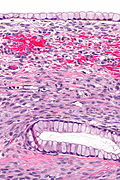

Ovarian mucinous cystadenoma. H&E stain. | |

| LM | cysts lined by a simple mucinous epithelium, no cytologic atypia |

| LM DDx | seromucinous borderline tumour of the ovary, mucinous borderline tumour of the ovary |

- Cysts lined by a simple mucinous epithelium.

- No cytologic atypia.